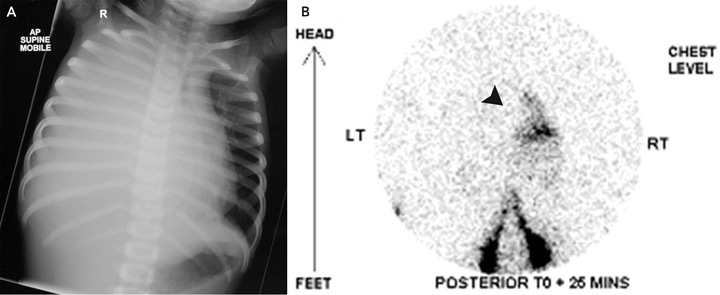

On examination, the patient’s temperature was 36.8°C, heart rate was 154 beats/min, respiratory rate was 67 breaths/min, and blood pressure was 96/68 mmHg. Her chest was dull to percussion, with poor air entry over the right hemithorax. The remainder of the physical examination was unremarkable. A chest x-ray (Box, A) revealed opacification of the right hemithorax with mediastinal shift to the left. An intercostal catheter (ICC) drained 900 mL of pink-stained milky fluid. Intravenous flucloxacillin and gentamicin therapy were begun for presumed empyema. She was transferred to a tertiary paediatric hospital.

Computed tomography of the chest excluded a mediastinal mass. Tests were negative for tumour markers, including α-fetoprotein, β-human chorionic gonadotropin and urinary biogenic amines. A Mantoux test returned a non-reactive result (diameter, 0 mm). Radionuclide lymphoscintigraphy (Box, B) confirmed normal lymphatic anatomy, but also detected rapid drainage of lymph into the right side of the chest.

Rupture of the thoracic duct between the diaphragm and the fifth thoracic vertebra results in accumulation of chyle in the right pleural space. In adults, lymphography has been used to define the anatomy, but is not practical in children due to difficulty cannulating lymphatics; for this reason, we used radionuclide lymphoscintigraphy instead. This showed leakage of chyle above the diaphragm on the right side. Disruption of the thoracic duct at this point was confirmed by thoracoscopy. As both our patient and the previously reported patient4 had right-sided chylothorax, the thoracic duct might be most susceptible to injury from forceful diaphragmatic contraction as it traverses the diaphragm. Hence, forceful vomiting is the most likely explanation in our patient.

Images used to diagnose a 2-year-old patient with spontaneous chylothorax